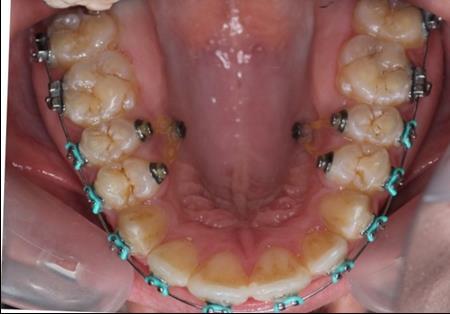

After obtaining the informed consent the orthodontic treatment began and 0,22 Roth straight-wire fixed appliances were bonded. After leveling and aligning, during upper arch expansion, we took impressions and made intermediate study models. We noticed that palatal cusps of the upper premolars could not be intruded by classic mechanics. We decided to intrude first and second bicuspids to resolve the open bite. Skeletal anchorage was indicated and two orthodontic mini-implants were inserted on the palatal side between the premolars.

Figure 4.Intraoral photography at the start of the treatment.

Intraoral photography at the start of the treatment.